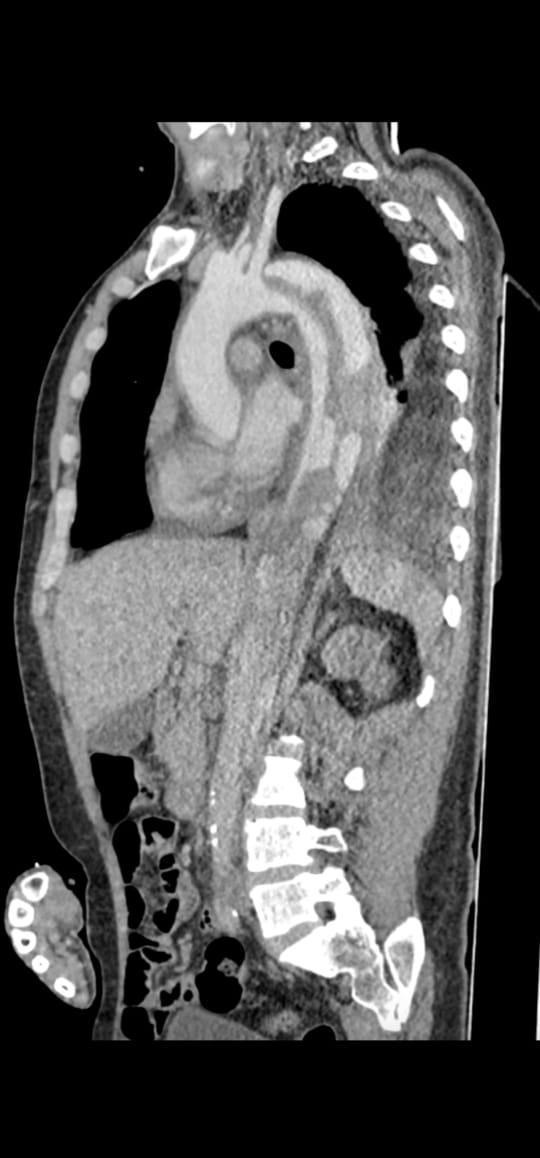

وأوضح بيان هيئة الرعاية الصحية، التدخل الجراحي تم على مرحلتين لمريض يبلغ من العمر 44 عامًا كان يعاني من انسلاخ بالشريان الأورطي النازل وتقرحات بقوس الشريان الأورطي وتجمع دموي بالشريان الأورطي الصاعد، حيث وصل المريض إلى قسم الطوارئ بالمستشفى في حالة حرجة يعاني من آلام شديدة بالصدر والظهر وارتفاع في ضغط الدم، وعلى الفور تم التعامل معه وإجراء الفحوصات اللازمة، ونقله للعناية المركزة للسيطرة على حالته ومنع تدهورها.

وتابع البيان، بناءً على التقييم الطبي للحالة تقرر إجراء تدخل مزدوج حيث تضمنت المرحلة الأولى إجراء عملية قلب مفتوح لاستبدال الشريان الأورطي الصاعد وإعادة توصيل شرايين الرقبة باستخدام شرايين صناعية، فيما شملت المرحلة الثانية تركيب دعامات مغطاة بالشريان الأورطي وقوسه باستخدام تقنية TEVAR وغلق الشريان تحت الترقوة باستخدام سدادة عبر القسطرة التداخلية تحت توجيه الأشعة التلفزيونية عن طريق المريء وتم تنفيذ التدخلين باستخدام أحدث التقنيات الطبية وبكفاءة عالية أسفرت عن تحسن ملحوظ في حالة المريض الذي غادر المستشفى بعد أسبوع من المتابعة الدقيقة وهو بحالة مستقرة الآن.